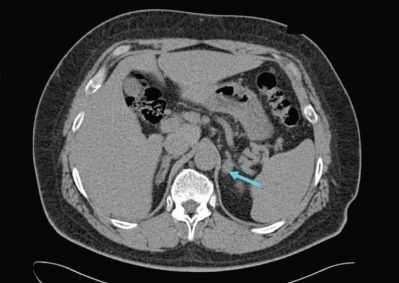

· КТ надпочечников – исключение патологии надпочечников, как причины первичной ХНН: уменьшение размеров, инфаркт надпочечников, опухолевые метастазы в надпочечники (чаще из легкого или молочной железы),амилоидоз надпочечников и т.д.;

- Компьютерная томография или магнитно-резонансная томография (КТ или МРТ) — может проводиться при стабильном состоянии, чтобы выявить причину кровоизлияния в надпочечники, например очаг инфекции в головном мозге, грудной клетке или брюшной полости, туберкулёз, опухоли и метастазы. КТ надпочечников при инфильтративном процессе не всегда информативна [1][21] .

- КТ надпочечников. Рентгенологическая визуализация рекомендована для обнаружения кровоизлияний, очагов дистрофии и других патологических признаков, которыми проявляется первичная надпочечниковая недостаточность. Для оценки структуры гипофиза показана рентгенография турецкого седла, КТ головного мозга.